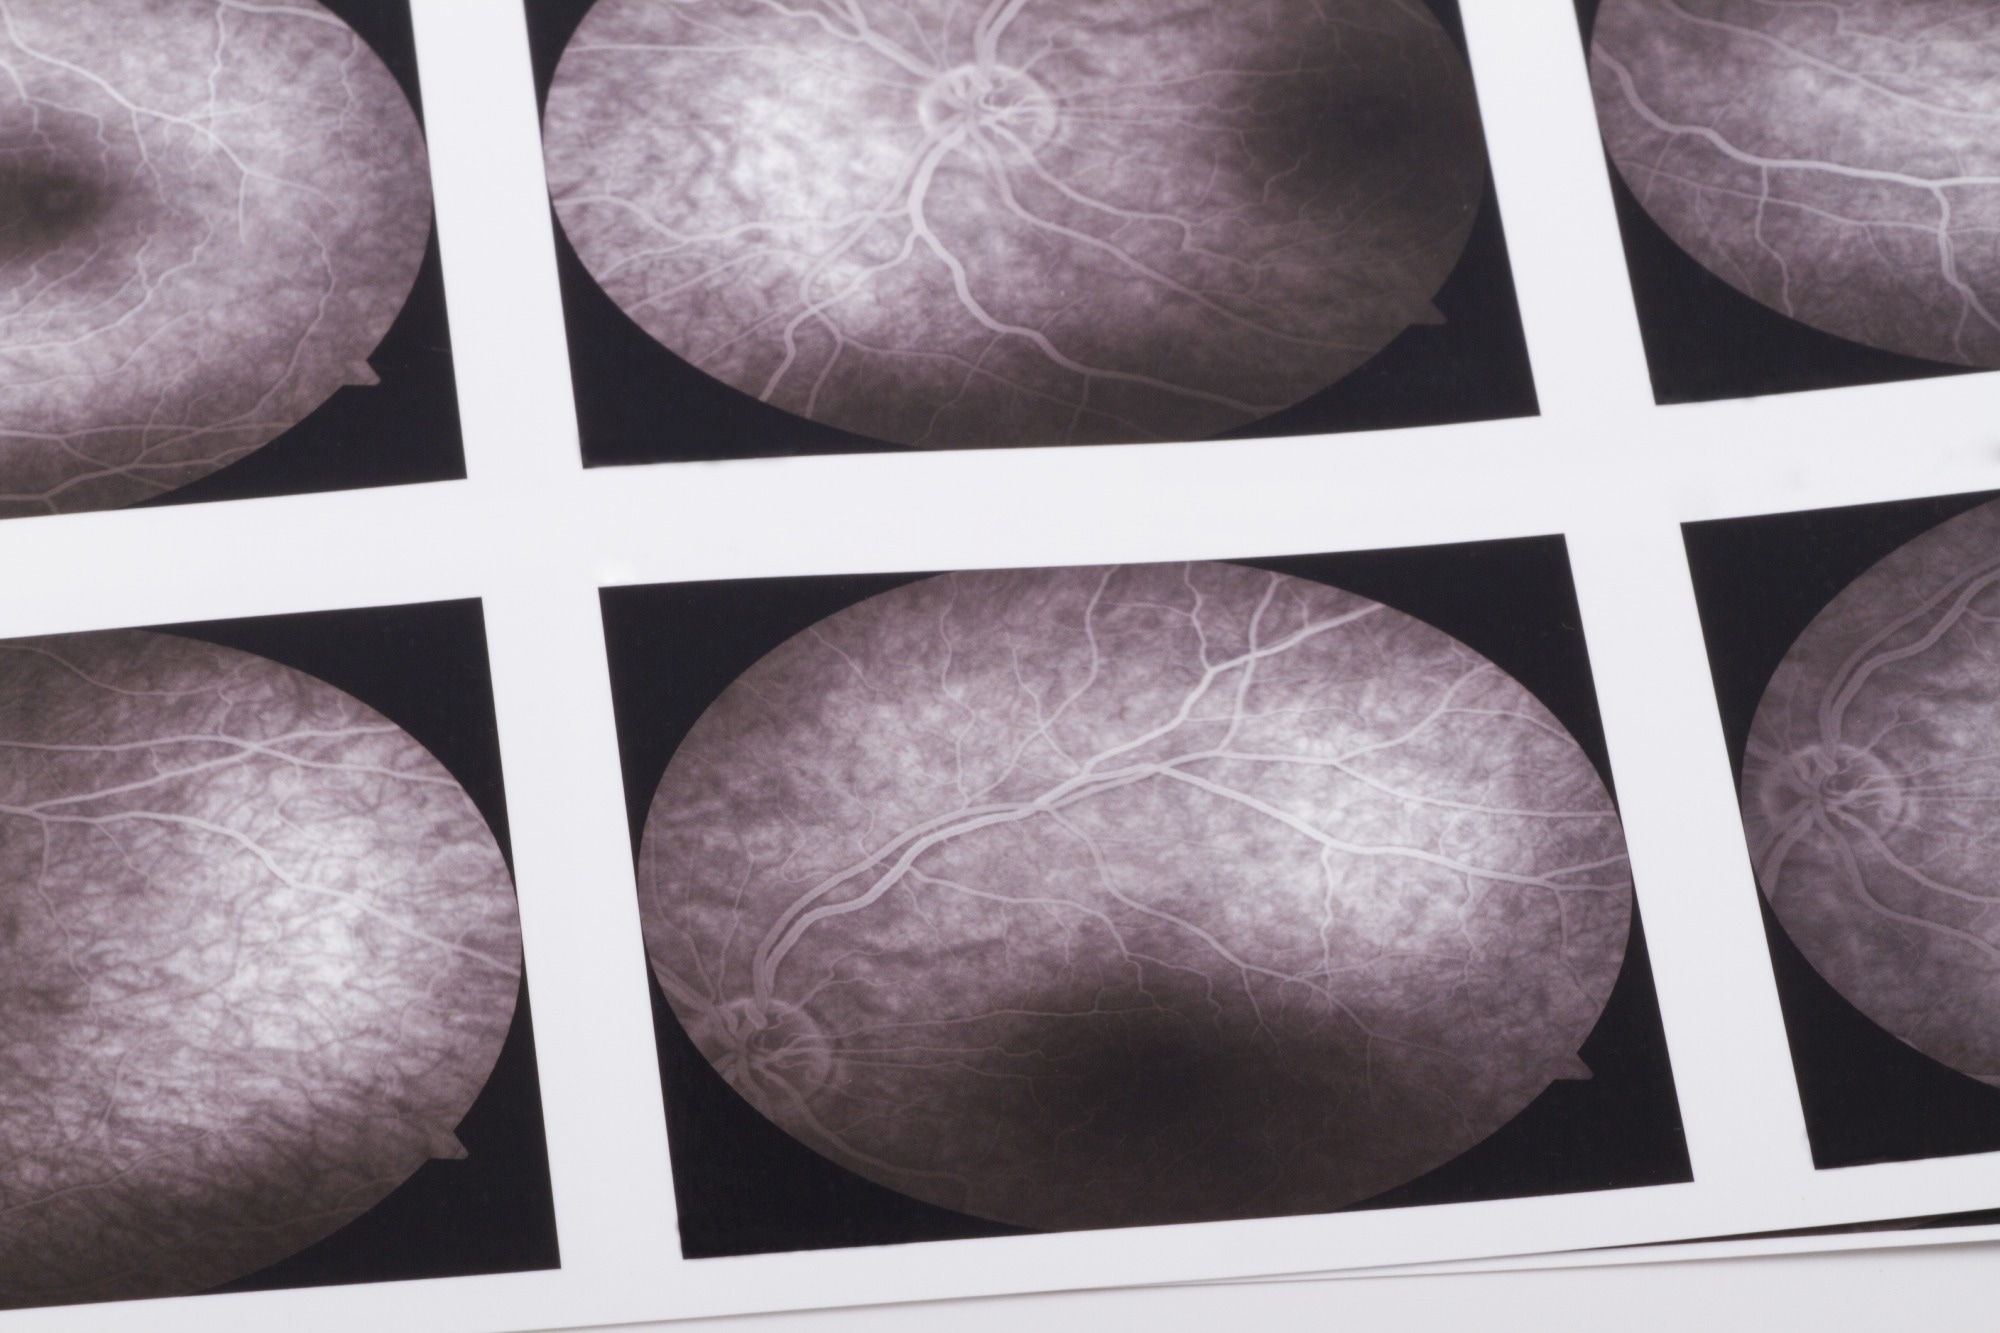

Study: Early detection of dementia through retinal imaging and trustworthy AI. Image Credit: bfk / ShutterstockStudy: Early detection of dementia through retinal imaging and trustworthy AI. Image Credit: bfk / Shutterstock

OCTA is a state-of-the-art imaging technique that allows for rapid and noninvasive imaging of the retinal microvasculature, including even the smallest capillaries with a resolution of 5–6μm. This technology provides detailed insights into the microvascular network and the structure of the foveal avascular zone across different retinal layers, as well as the choroid.